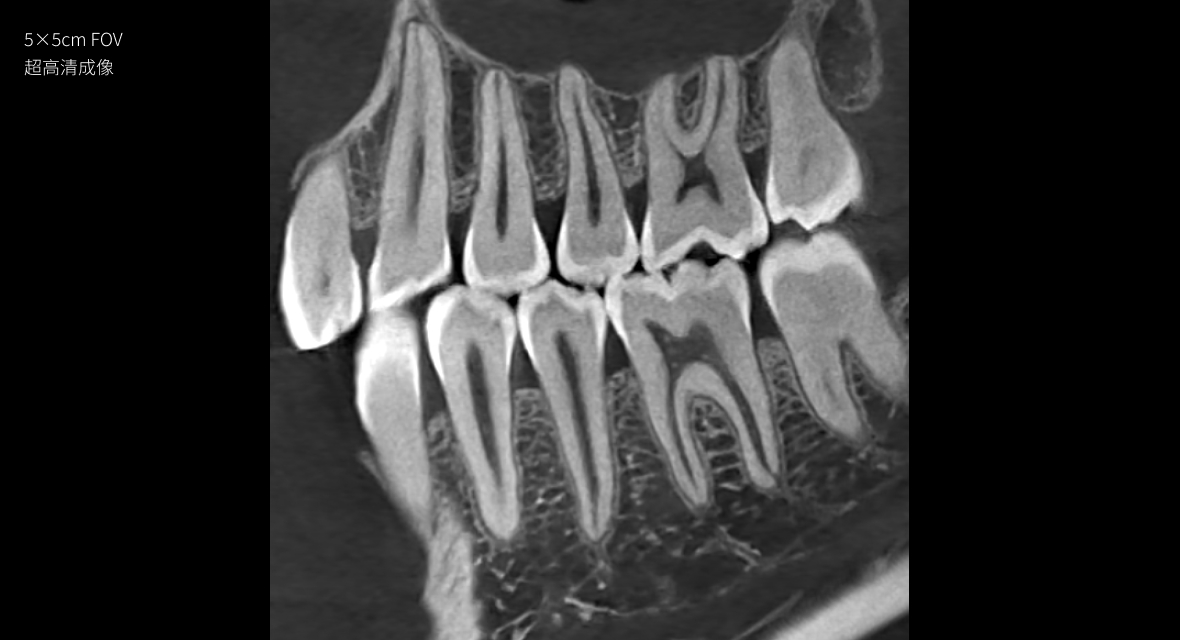

超高清成像

Pirox-A的小视野超清模式,采用旋转阳极射源成像。旋转阳极射源的亮度更高,焦点尺寸可以达到惊人的0.3mm,让Pirox-A可轻松捕捉细微玄妙之处。此外,旋转阳极通过不断旋转,可以大大增加散热面积,降低球管热累积进而提升连续工作能力。